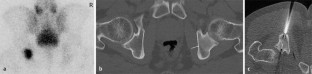

Abb. 1